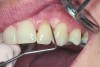

Following active therapy, probing depths of 4 mm or less (Figure 1 and Figure 2) and the absence of bleeding on probing contribute to improved health and stability. Increasing probing depths should alert the therapist to identify etiology and determine whether active periodontal therapy is warranted. The absence of bleeding on probing is a strong predictor of stability, and although the presence of bleeding does not always result in attachment loss, it remains an important parameter to evaluate.14 Bleeding on probing is also an important parameter for assessing implant health during maintenance. Serino et al15 evaluated 27 patients with 19 dental implants over 5 years. Patients were seen every 6 months and they concluded that bleeding on probing was a good predictor for attachment loss and disease progression around the implants (Figure 3).

Fig 1. A deep pocket of 7 mm prior to active periodontal therapy.

Figure 1

Fig 2. Following periodontal regenerative therapy, the tooth with a 3-mm probing depth, which facilitates maintenance.

Figure 2